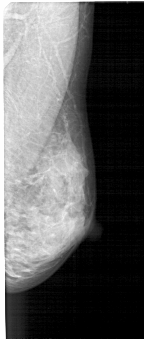

A_1446_1.LEFT_CC

LEFT_CC LINES 4711 PIXELS_PER_LINE 2296 BITS_PER_PIXEL 12 RESOLUTION 43.5 OVERLAY